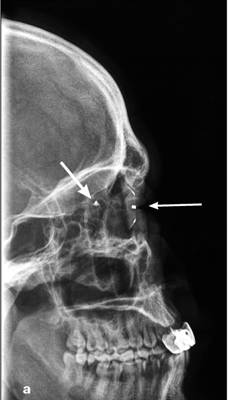

Рентгенологическое исследование глаза с протезом

Комберга-Балтина

Выполняется для определения локализации

инородных тел. Протез Комберга-Балтина представляет собой контактную линзу со

свинцовыми метками по краям протеза. Снимок производят в носоподбородочной и

боковой проекциях при фиксации взора на точке, находящейся прямо перед глазами.

Локализацию инородных тел по снимкам осуществляют с помощью схем-измерителей

(рис. 3).

Рис. 3. Рентгенограммы глазного яблока с

протезом Комберга-Балтина (тонкая стрелка) в боковой (а), аксиальной (б)

проекциях. Инородное тело глазницы (толстая стрелка)